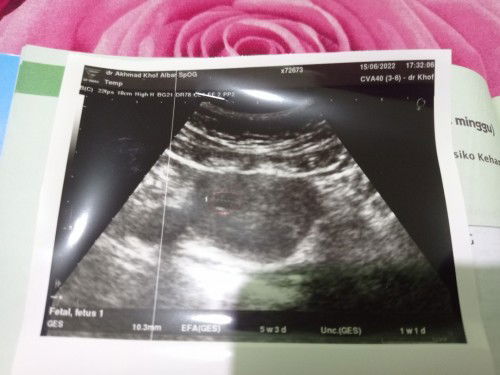

Bun mau sharing.. Hari rabu malam kemarin saya datang ke spOG dengan keluhan keluar sedikit flek berlendir disetai dengan nyeri perut. Saat di usg difonis BO atau kehamilan kosong, Disuruh kuret sama spOG tp saya menolak.. Dan besok paginya saya coba datang ke spOG lain dan difonis sama spt yg pertama. Saat disuruh kuret saya berusaha menolak dan mnta waktu 2 minggu untuk melihat apa ada perkembangan pada kehamilan saya.. Sejujurnya saya masih ingin mempertahankannya n berharap kehamilan saya ada perkembangan, toh keluar fleknya cuman sedikit itu pun tdk sampai nempel dicelana dalam.. Sekarang usia kehamilan saya 9w.. Hari ini badan saya terasa lemas agak pusing dan mual2 dan keluar sedikit flek lagi dan masih merasakan nyerii di perut dan pinggul.. Minta sarannya dong bun sebaiknya saya menjalani kuret yg di saranin spOG apa nunggu dulu 2 minggu.. Td malam saya juga merasakan nyeri diperut bawah dan dipinggul.. Saya harus giman bun.. 😭😭 #seriusnanya #bantusharing #pleasehelp

Hallo bunda mau tanya.. sekarang usia kehamilanku 8w5d. td saya coba usg karna keluar flek, kata dokter kehamilanku hanya ada kantungnya saja gak ada janinnya atau disebut hamil kosong.. disuruh kuret sama dokter.. Gimana ini bunda padahal ini hamil pertama saya sudah 5 tahun menantikannya.. Harus gimana bunda #seriusnanya #bantusharing #ingintahu #firstmom #pleasehelp